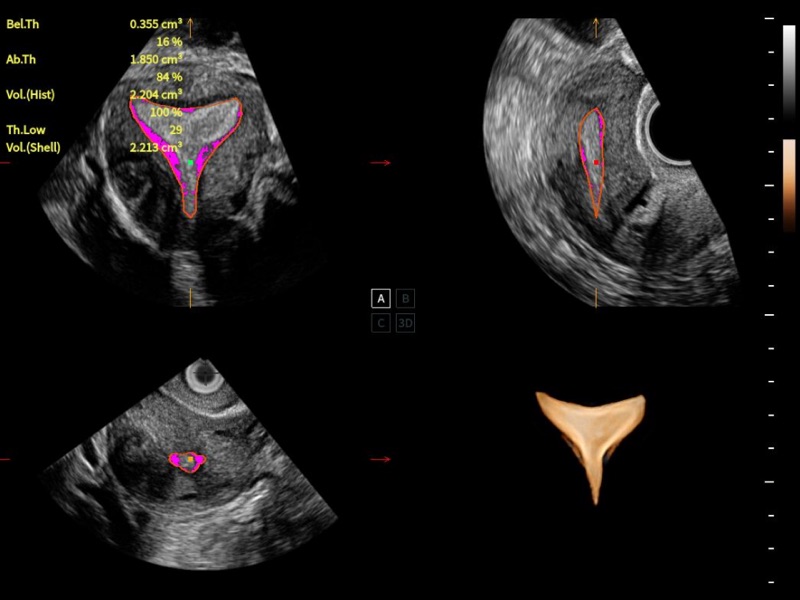

VOCAL

婦科自動(dòng)測(cè)量

三維卵泡自動(dòng)測(cè)量